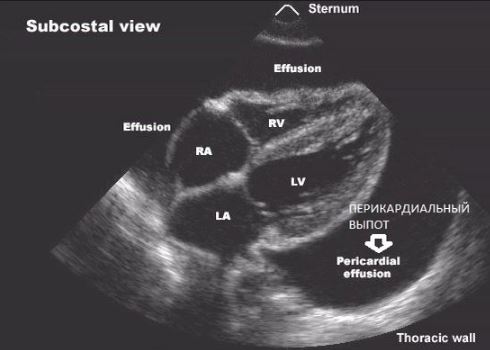

- ультразвуковое исследование (УЗИ) сердечной мышцы – позволяет определить расширение сердечных камер и присутствие в них экссудата (воспалительной жидкости);

УЗИ при перикардите - рентген сердца – рентгенографический признак кардита – увеличение размеров мышцы;